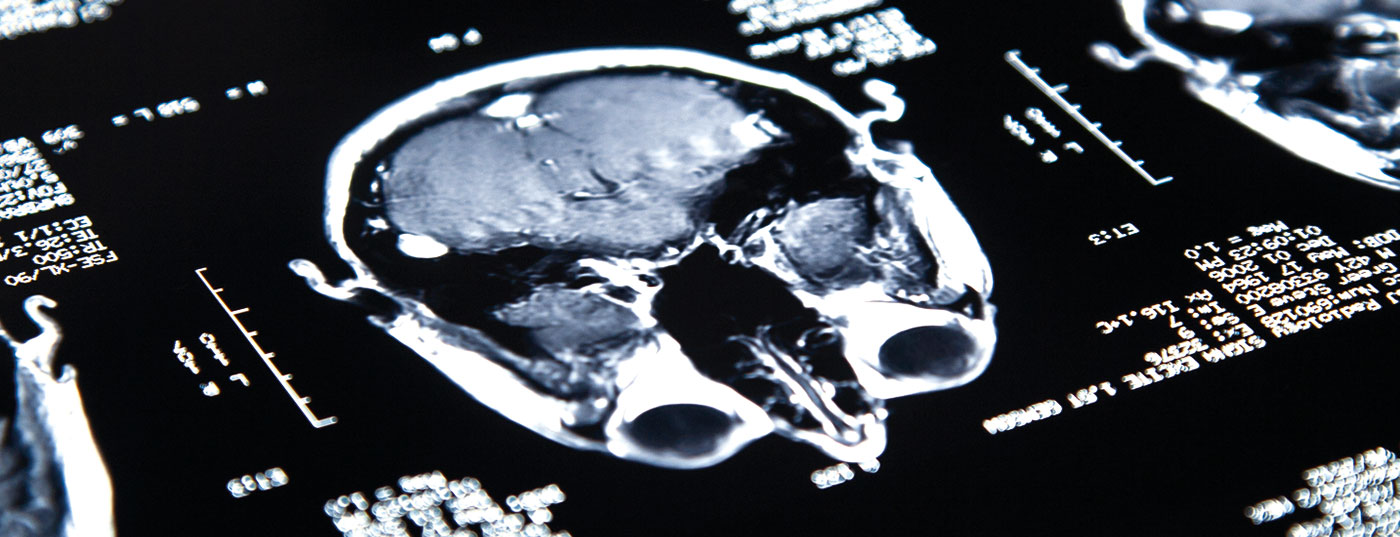

Während Immuntherapien bei anderen Entitäten rasch auf dem Vormarsch sind, stecken sie bei ZNS-Tumoren noch in den Kinderschuhen. Dies liegt unter anderem an der oftmals geringen Immunogenität. Dennoch könnten Antikörper-basierte Therapien, Impfungen und CAR-T-Zellen in den nächsten Jahren auch bei Gliomen an Bedeutung gewinnen.